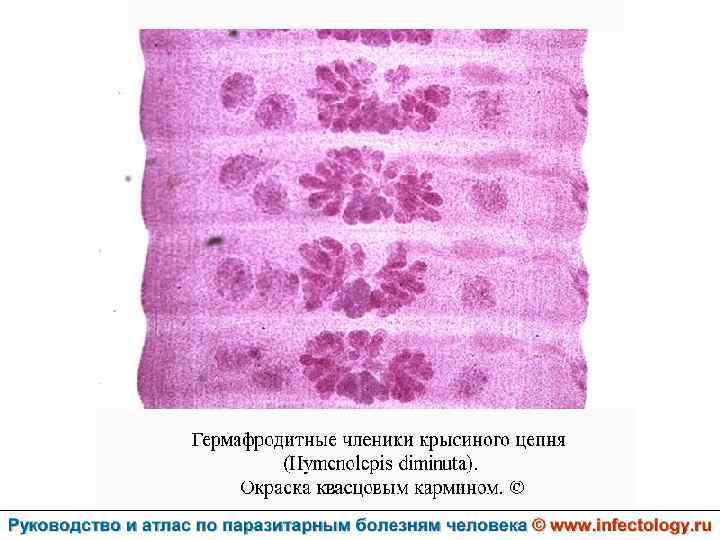

Гименолепидоз крысиный (диминутный) (шифр по МКБ 10 – B 71. 0) – зоонозный гельминтоз, для которого человек является случайным хозяином. Характеризуется нарушением деятельности пищеварительной и нервной систем.